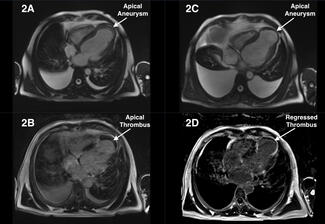

Byeng-Ju Son, MD; Jong-Seon Park, MD, PhD; Ung Kim, MD, PhD; Kang-Un Choi, MD, PhD; Jong-Il Park, MD

Byeng-Ju Son, MD; Jong-Seon Park, MD,...

An 82-year-old woman was admitted for non-ST elevation myocardial infarction. At the coronary angiography, diffuse significant stenosis of the right coronary artery was observed.

An 82-year-old woman was...